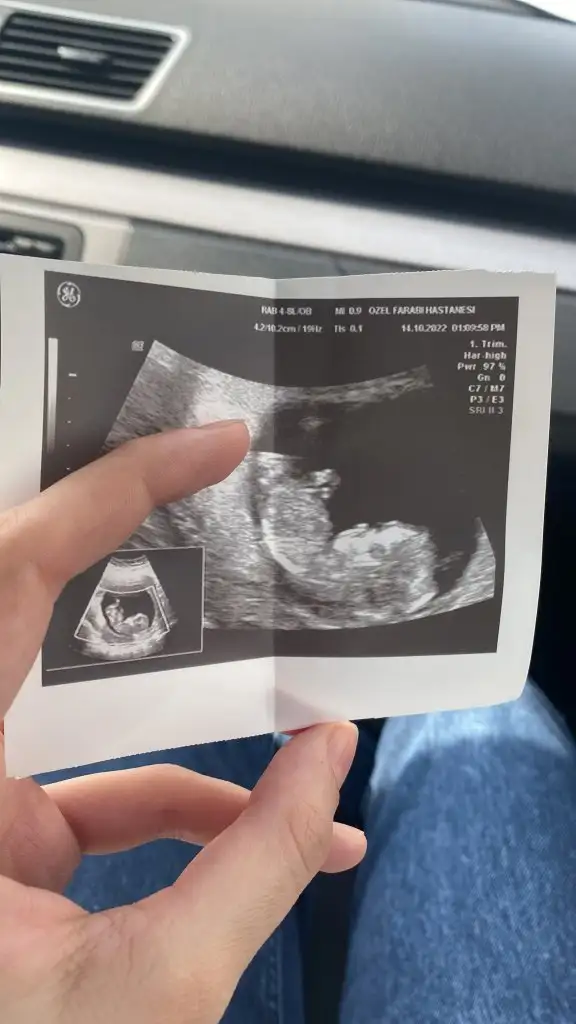

KızMerhaba arkadaşlar, 14. Haftamızdayız cinsiyet hala belli değil. Dr'umuzda 16. Haftada söylemek en doğrusu olur dedi. Ama tabiki merak iştevarsa aranızda tahmin yapabilenler veya ultrason görüntüsünden anlayanlar.tahminlerinizi alabilirsem sevinirim : )